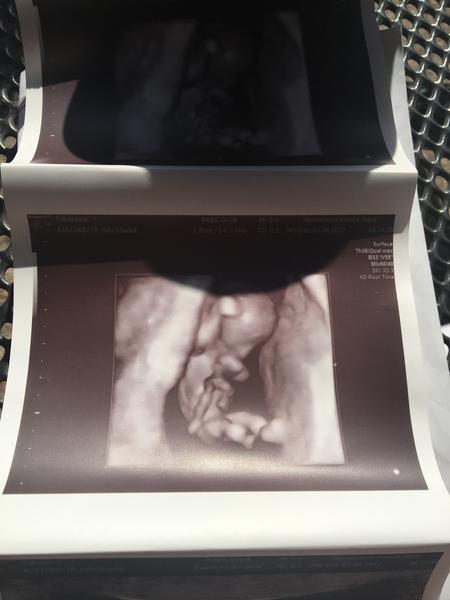

Ahojte babulky tak mame po 3D sone som aj veľmi šťastná a zároveň aj Smutná aj slzy boli..babo je vitálne zdravé staršie o týždeň tak sa zase santilo a asi to bude dievčatko moja ďalšia babulka upresni v 20tt či je to na 100% lebo sa uškrnul a usmial keď to povedal vie žeby som prijala chalana..A to smutne je že prišiel nato že som čakala dvojičky druhé babo sa prestalo vivijat v 5-6tt aby sa somnou iný dr nehádali že je to hematóm nech má nestrasia..ale že sa nemám obávať

A tu je moja pipinka som zabudla teším sa veľmi a meriame 5,8cm termín pôrodu sa mám posunul na 16.12. Už 😍